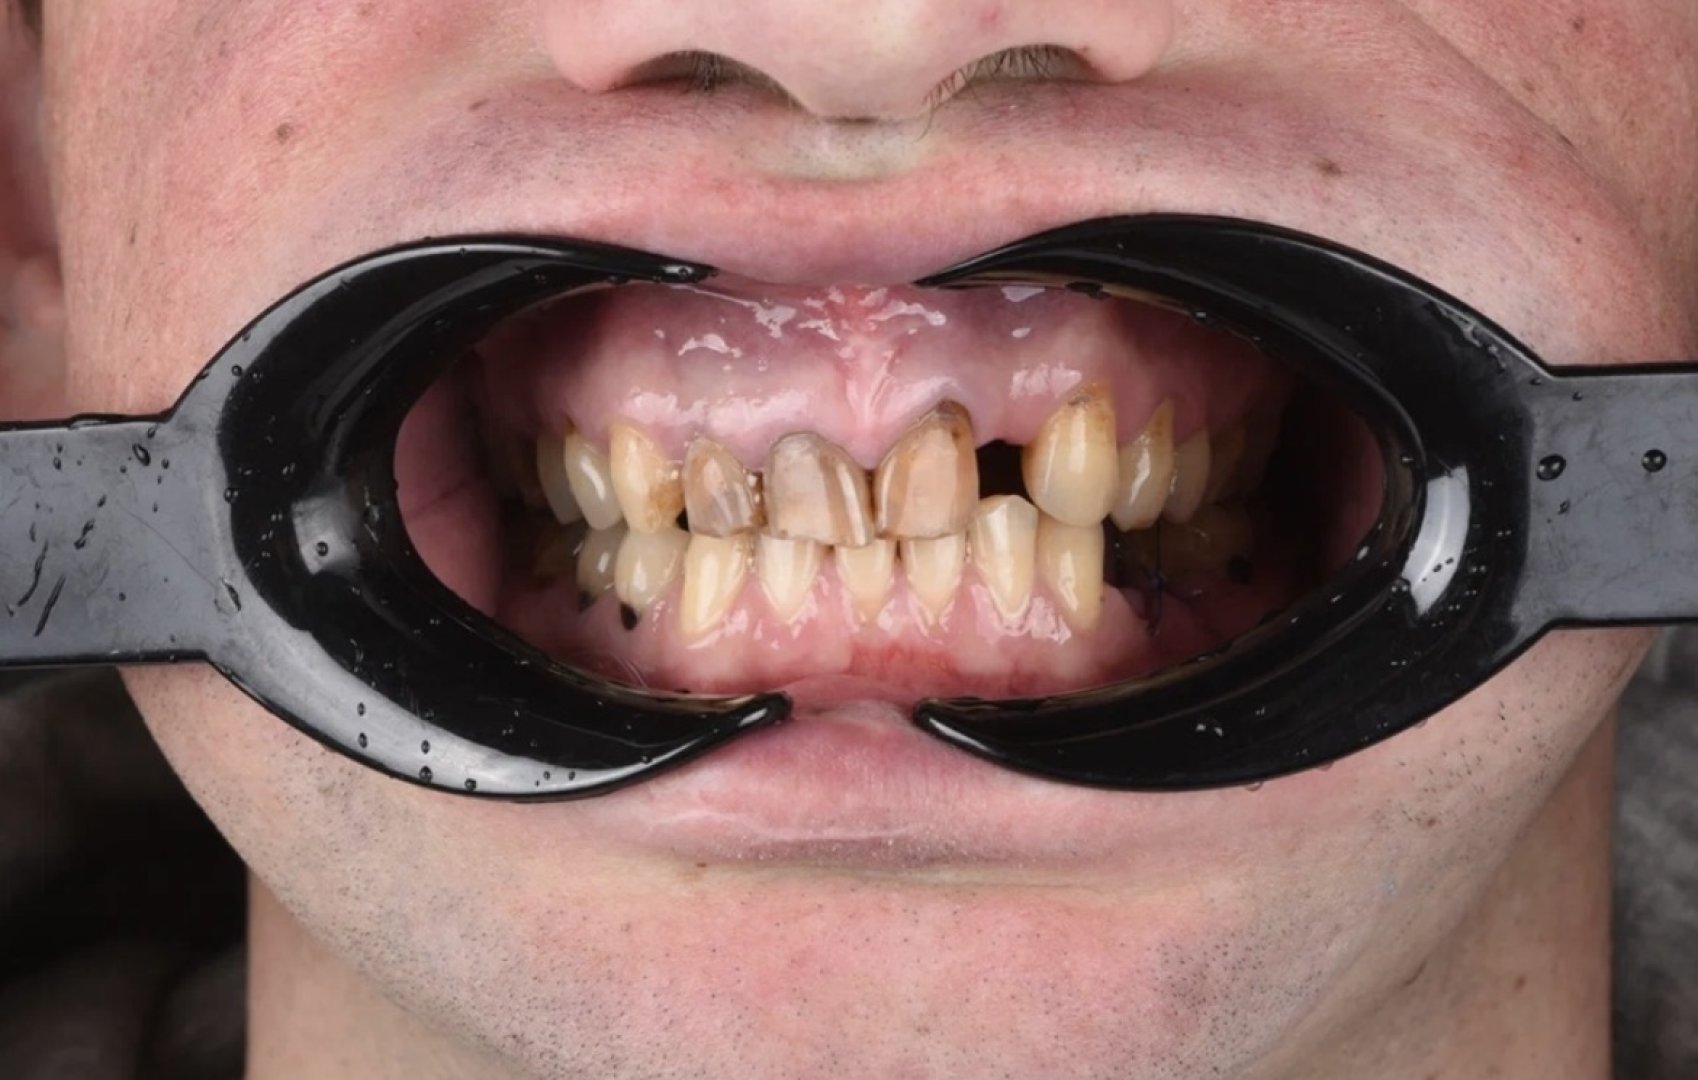

Обточка зубов 12-23 под дц коронки, ретракция 000 и 00 нитями, снятие рабочих оттисков а-силиконом, изготовление временных акриловых коронок прямым методом через силиконовый ключ, фиксация на TempBond.